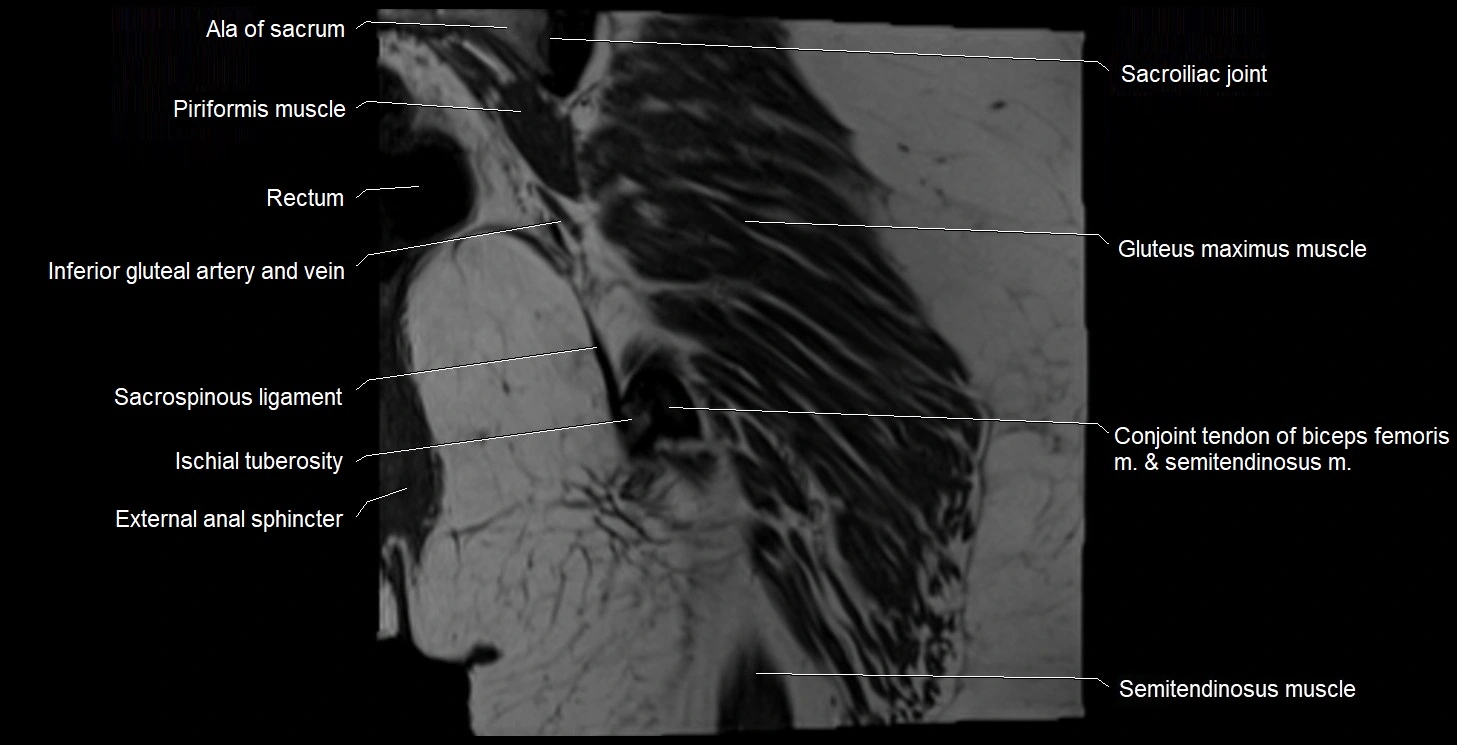

- Ala of sacrum

- Conjoint tendon of biceps femoris & semitendinosus

- External anal sphincter

- Gluteus maximus muscle

- Inferior gluteal artery

- Ischial tuberosity

- Ischioanal fossa

- Rectum

- Sacroiliac joint

- Sacrospinous ligament